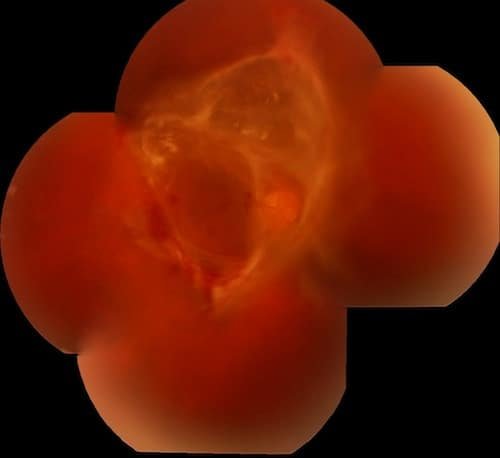

Retinopatía Diabética proliferativa severa con hemorragia vitrea.

Panfotocoagulación reciente con endolaser.